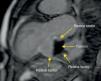

Em virtude de queixas de dispneia e dor retroesternal recorrente, sem alterações eletrocardiográficas de novo e sem elevação dos biomarcadores de necrose miocárdica, o doente fez TAC torácica, que mostrou uma massa hipodensa aparentemente extracardíaca, em relação com a aurícula esquerda. Um segundo ecocardiograma foi então realizado, tendo-se observado uma massa adjacente à aurícula esquerda (39×40mm), cuja continuidade com as cavidades cardíacas era duvidosa (Figuras 1 e 2). Foi então efetuada uma Ressonância Magnética Cardíaca que demonstrou a presença de um volumoso aneurisma ínfero-basal do ventrículo esquerdo, parcialmente preenchido por trombo de grandes dimensões (52×48×32mm). Dada a reduzida espessura da parede deste aneurisma, não foi possível distinguir nela as várias camadas da parede, pelo que não se pôde excluir em definitivo um pseudo-aneurisma com apresentação tardia. Existia algum fluxo entre o trombo e o fundo-de-saco do aneurisma que, no entanto, parecia aderente às paredes do aneurisma nas extremidades superior e inferior (Figuras 3 e 4). Este exame confirmou o compromisso severo da função ventricular esquerda e a insuficiência mitral, por alteração da geometria do ventrículo esquerdo, com marcado repuxamento do folheto posterior.

DiscussãoO diagnóstico entre aneurisma ventricular esquerdo e pseudo-aneurisma é difícil, especialmente quando o aneurisma tem uma localização posterior (3%)2,3. Os verdadeiros aneurismas são definidos como áreas de miocárdio mais fino, discinético, mas constituído por todas as camadas da parede. Por outro lado os pseudo-aneurismas resultam da rotura da parede livre, contida muitas vezes por trombo e pericárdio aderente. Os pseudo-aneurismas do ventrículo esquerdo apresentam assim maior risco de complicações, quando comparados com os aneurismas verdadeiros, sendo a mais grave a rotura espontânea, que resulta geralmente em morte súbita. O diagnóstico diferencial das duas situações é difícil, sendo muitas vezes um diagnóstico cirúrgico, pois têm muitas características comuns4. Um miocárdio fino ou com rotura move-se discineticamente ou não contrai, conduz à ocorrência de insuficiência cardíaca e arritmias ventriculares malignas, podendo estas ocorrer em ambas as patologias5. A deteção da massa adjacente à aurícula esquerda pela TAC e ecocardiografia tornou-se um desafio diagnóstico. A Ressonância Magnética Nuclear confirmou a existência de trombo associado a aneurisma/pseudo-aneurisma. No entanto, a dificuldade de detetar a continuidade do miocárdio, manteve-se com esta técnica. A intervenção cirúrgica, nos casos de aneurisma verdadeiro, visa melhorar a função do ventrículo esquerdo e reverter o remodelling, reduzindo a probabilidade de arritmias malignas, eventos embólicos e assim melhorar a sobrevida dos doentes com esta complicação.